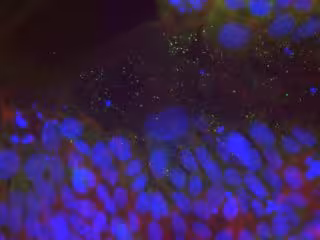

Microscopia epifluorescencia

Microscopia epifluorescencia - CSIC